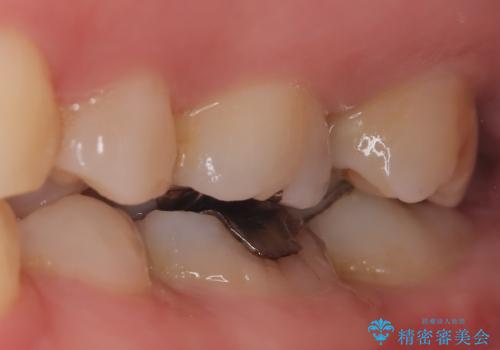

- メタルフリーを主訴に来院されました。

歯牙の破折を防ぐために、セラミッククラウンにて修復しています。